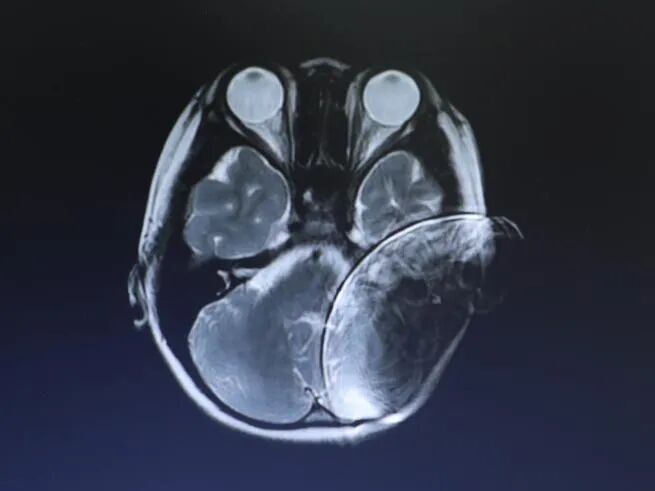

儿童用户 年龄9岁 左侧植入SYNCHRONY人工耳蜗

核磁检查原因:评估对侧能否植入耳蜗

影片清晰度很高,完全满足诊断和评估需求。

影片显示耳蜗侧有较小伪影存在,但对侧的听神经和耳蜗显示的非常清晰,小朋友的耳蜗和内听道完全没有问题,左侧大脑也没有问题,所以经过核磁报告评估,这个小朋友完全适合对侧人工耳蜗植入。